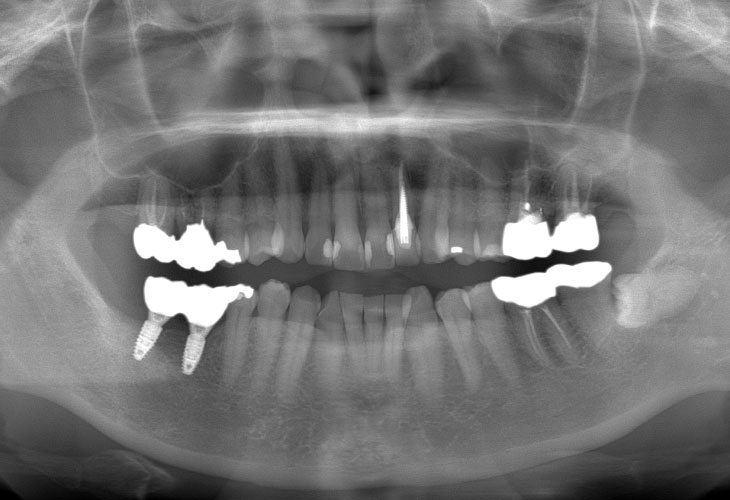

下顎臼歯部インプラント治療(2本)

主訴 右下奥歯の歯が無い。インプラント治療をしたい。

右下臼歯部欠損

治療内容 インプラント(右下6・7)

インプラント: 4ヶ月/6回